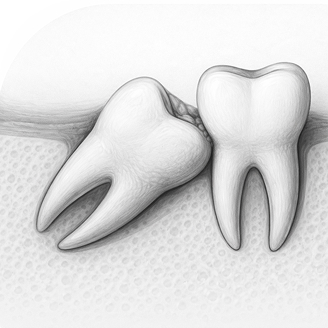

Чаще всего проводится удаление ретенированных и дистопированных зубов — обычно это зубы мудрости, которые не прорезались полностью или растут неправильно. В зависимости от ситуации удаление может быть разной степени сложности. Перед процедурой врач обязательно делает снимок и выбирает оптимальный способ лечения.